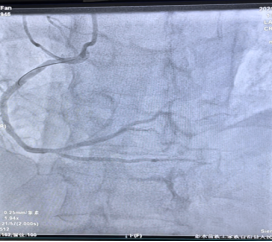

第1例是一位老年男性患者,2年前曾在外院行冠状动脉内支架植入术,平时未规律服用抗血小板药物,因“呼吸困难”来院就诊,冠状动脉造影提示左主干开口狭窄约80%,右冠开口狭窄约70%,患者经治疗后好转出院,预约择期行IVUS指导下处理左主干病变。在陈元友主任医师的指导下,王欣主治医师将IVUS导管放置在血管远端,采取自动回撤模式,测得左主干开口面积为2.9mm2,已经达到介入手术指征,在左主干开口成功植入1枚支架,术后IVUS测得左主干开口面积为12.7mm2,,术后支架贴壁良好,患者左主干病变解除,患者术后恢复良好。(见图1)。

图1(左图为术前,右图为术后)